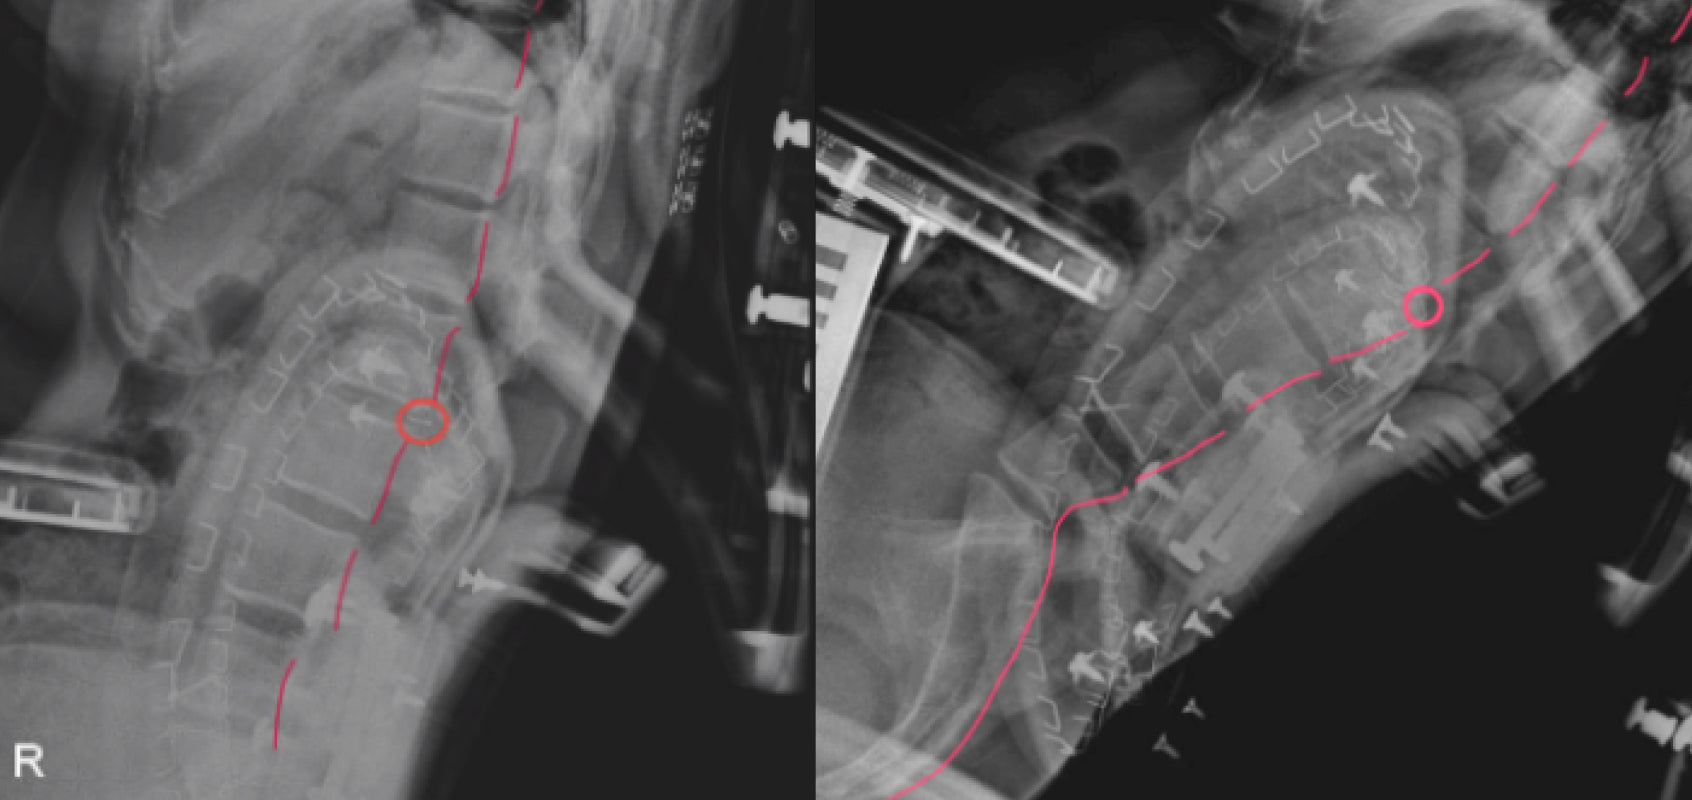

Wir haben auch festgestellt, dass Stühle mit ausgeprägten Lendenwirbelüberhängen die natürliche Krümmung der Wirbelsäule stören können, wie Röntgenaufnahmen zeigen. Dies führt zu unnatürlichen Brüchen in der Ausrichtung der Wirbelsäule und erhöht den Druck auf bestimmte Segmente der Wirbelsäule.

* Quelle: LiberNovo Internes Labour